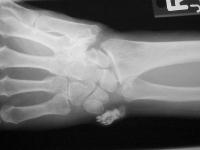

Isolated involvement around the flexor carpi ulnaris at the level of the wrist.